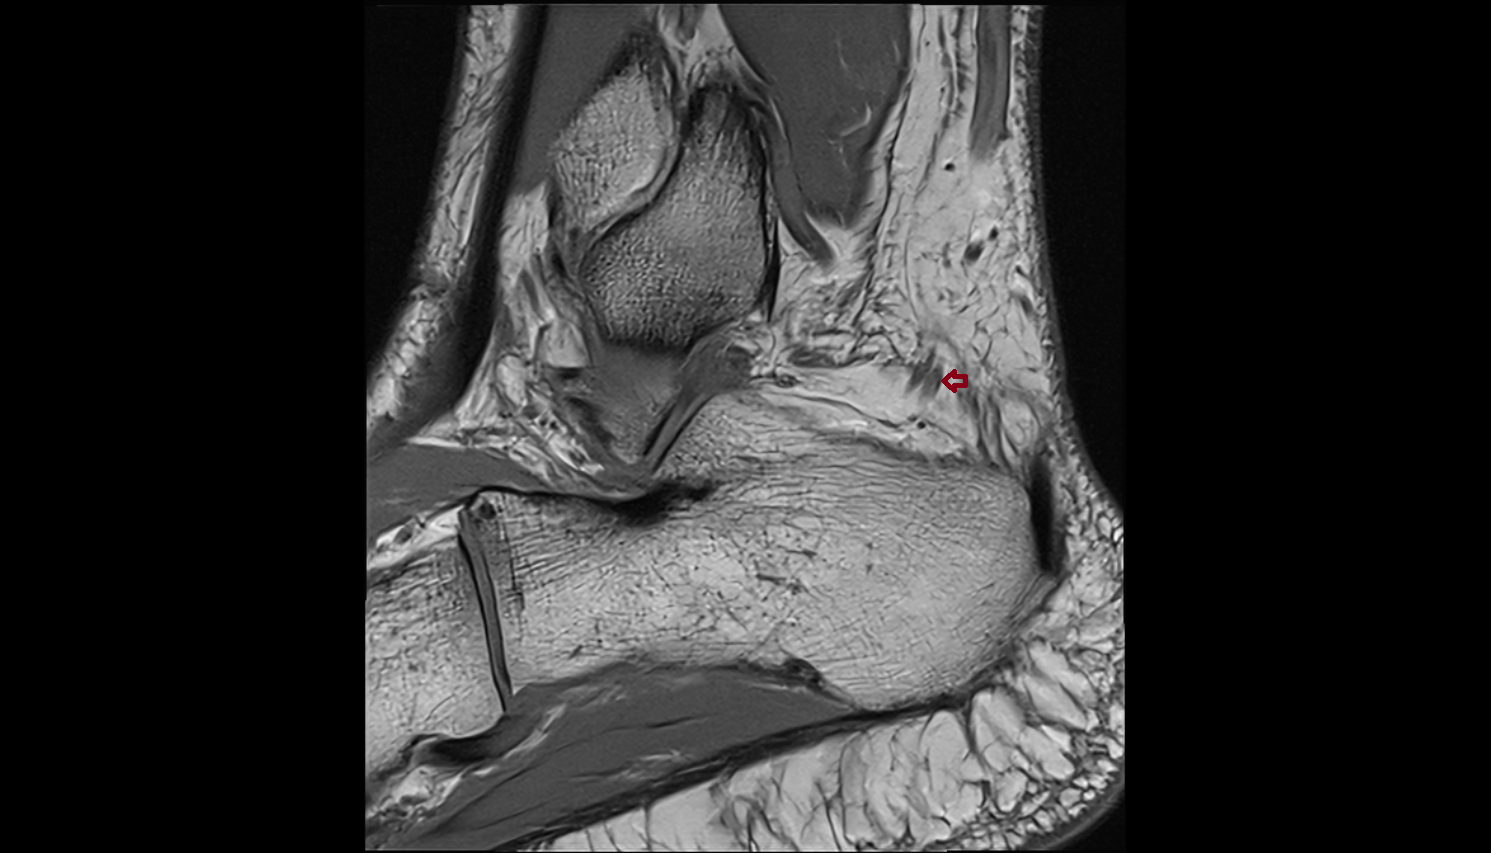

- Talus

- Head of talus

- Body of talus

- Neck of talus

- Calcaneus

- Ankle joint

- Talocalcaneal joint